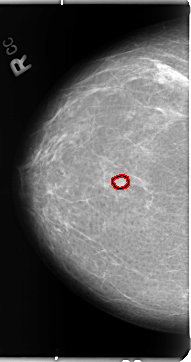

B_3103_1.RIGHT_MLO

FILE: B_3103_1.RIGHT_MLO.OVERLAY

TOTAL_ABNORMALITIES 1

ABNORMALITY 1

LESION_TYPE MASS SHAPE OVAL MARGINS CIRCUMSCRIBED-ILL_DEFINED

ASSESSMENT 3

SUBTLETY 3

PATHOLOGY BENIGN

TOTAL_OUTLINES 1

BOUNDARY